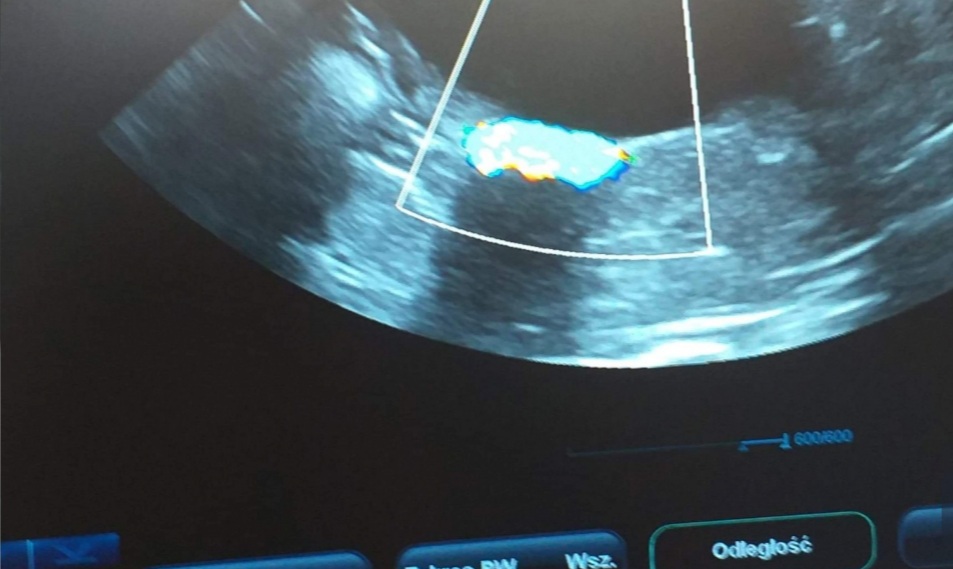

Gdyby nie Mikuś, nie prosiłabym Was o pomoc, ale on jest naszym słoneczkiem i chcemy mu pomóc. Post będzie długi, ale będę wdzięczna za przeczytanie. Mam na imię Karolina, mamy z chłopakiem trzy koty i psa. Ze względu na stan zdrowia pracuję w sklepie na pół etatu, mój chłopak w czasie koronawirusa został zwolniony, szuka pracy i pracuje dorywczo na czarno. Dotychczas jakoś sobie radziliśmy, było skromnie, ale byliśmy razem i mieliśmy cudowne zwierzaki. W styczniu nasz kocurek Mikuś zaczął chorować pojawił się krwiomocz, problemy z wypróżnianiem, pozycja bólowa, napięty brzuch. Pojechaliśmy do weterynarza i okazało się, że Mikuś ma w moczu mnóstwo kryształków struwitów i całkowicie zatkane jelita :( Został w klinice, poddano go narkozie, zrobiono lewatywę, badania moczu, dostał zastrzyki przeciwbólowe, rozkurczowe, antybiotyki, kapsułki na rozcieńczenie moczu i zalecenie karmienia dobrą mokrą karmą. Zapłaciliśmy 350 zł, później dodatkowo dokupiliśmy kapsułki za 65 zł, do tego karma urinary. To był dla nas ogromny strzał finansowy, bo dotychczas wystarczyło nam na opłatę mieszkania, rachunków i bardzo skromne jedzenie dla nas i zwierząt (a właściwie głównie dla nas, bo często woleliśmy kupić coś lepszego zwierzakom niż sobie). Niestety problemy Mikusia nawracały. Każda wizyta u lekarza to koszt 150-200 zł. Kolejne kapsułki, kolejna karma specjalistyczna i powoli zaczęliśmy się załamywać, czy damy radę temu sprostać finansowo. Nie chcemy oddawać naszego ukochanego kota, nie wyobrażamy sobie tego, ale w tym momencie nie stać nas na jego leczenie, badania i leki. Chcę założyć zbiórkę dla Mikusia, ale trochę trwa zanim zostanie ona zweryfikowana. Dlatego tutaj proszę o pomoc: jeśli komuś zostały po leczeniu kota kapsułki zakwaszające mocz, jeśli ktoś ma jakiś nadmiar puszek wysokomięsnych, których Wasze koty z jakiś powodów nie jedzą, karmę dla psow i mógłby nam pomóc to będę bardzo wdzięczna.